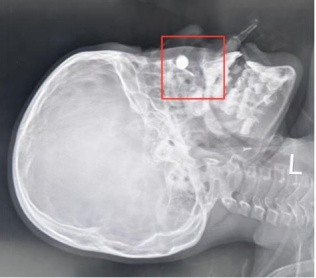

X线平片服从浮现,患儿鼻腔深处有一枚高密度圆形异物影。这个发现不仅诠释了MRI伪影的泉源,也让诊疗念念路出现了新的标的。

患儿鼻腔位置有个白色圆形高密度影,辅导异物